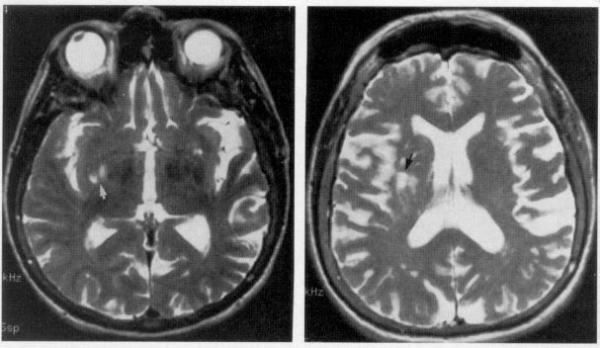

In the end, Badre says what makes anosognosia difficult in psychiatry is a lack of neuroscientific data on the topic. “I don’t think we have evidence that schizophrenia intrinsically makes the brain have this issue.”

Maybe not, argues DJ Jaffe, founder of the think-tank Mental Illness Policy Org and an advocate for the severely mentally ill, but a variety of brain-imaging data shows that the brain of someone with schizophrenia functions differently compared to a neurotypical brain.